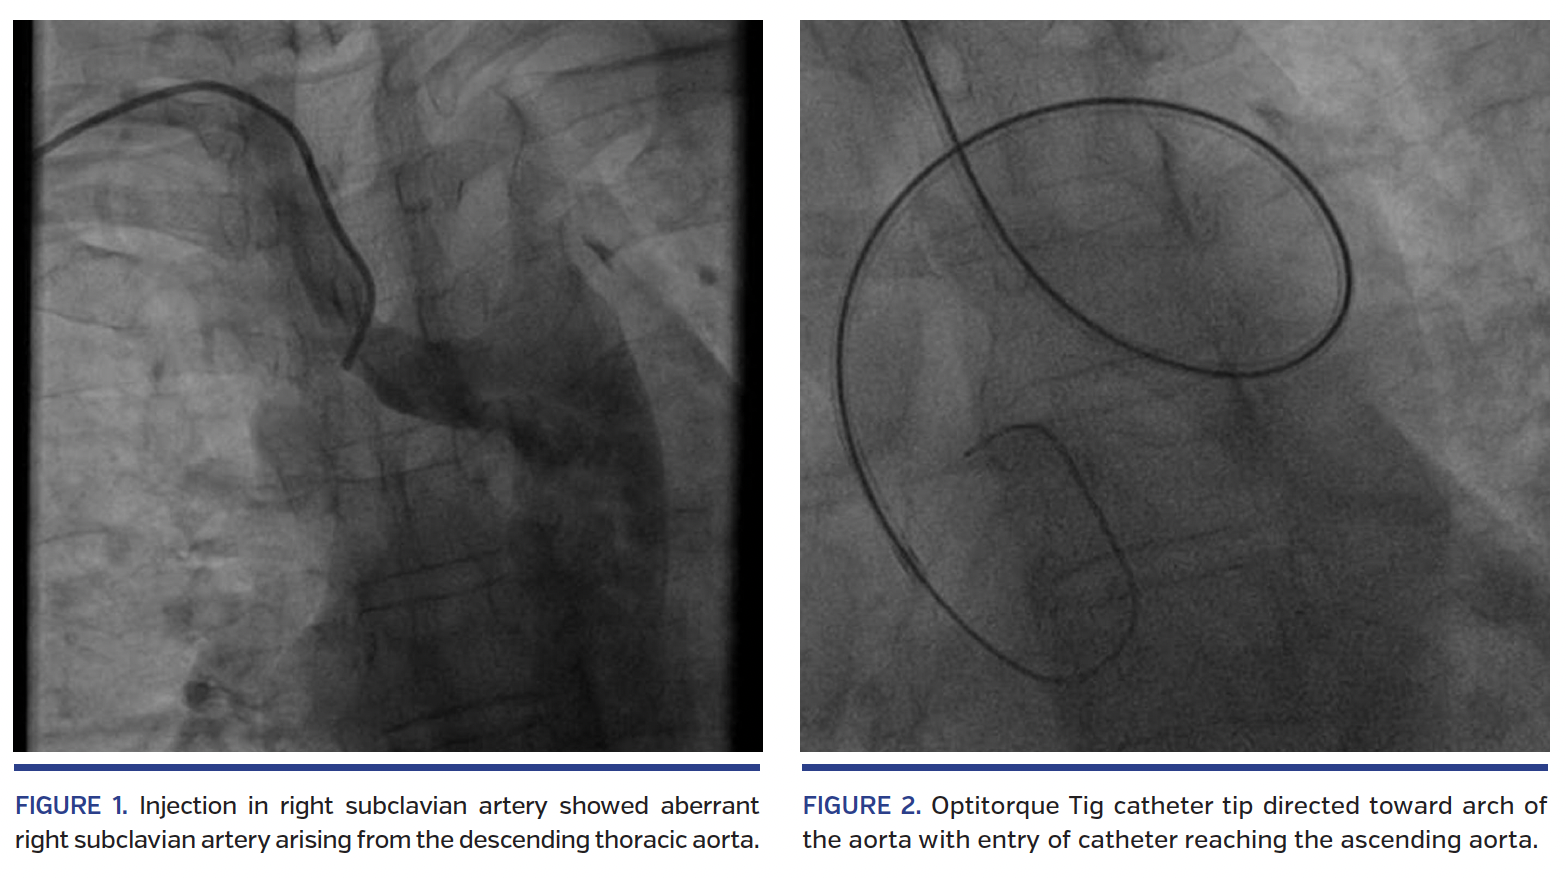

A 56-year-old male diabetic was admitted with diagnosis of evolved anterior-wall myocardial infarction (MI) with post-infarct angina. The results of a physical examination were unremarkable. Electrocardiogram showed features of evolved anterior-wall MI and cardiac biomarkers were elevated. Echocardiography showed hypokinesia in the left anterior descending (LAD) territory; left ventricular ejection fraction was 45%. Coronary angiography via right radial artery was planned. During coronary angiography, a 0.035˝ guidewire (Terumo) repeatedly entered the descending thoracic aorta. Contrast injection in the abnormal artery showed right subclavian artery arising from descending thoracic aorta (Figure 1; Video 1). However, with the tip of the Optitorque Tig catheter (Terumo) directed toward the aortic arch, the guidewire could enter the arch and ascending aorta (Figure 2; Video 2). The right coronary artery was cannulated with the Optitorque catheter with difficulty (Figure 3; Video 3), but it was not possible to cannulate the left coronary artery with the same catheter. The Optitorque catheter was exchanged to a 3.5 Extra Backup 6 Fr guide catheter and the left coronary artery was engaged cautiously with the help of the reverse end of a 0.035˝ guidewire taking a E-shaped loop (Figure 4; Videos 4A and 4B). The right coronary artery was normal and the mid LAD showed focal critical stenosis. The LAD was stented with a 2.5 x 18 mm drug-eluting stent. Later, esophagogram with contrast swallow revealed posterior oblique indentation of the proximal esophagus in relation with the catheter in the right subclavian artery (Figure 5; Video 5). Subsequently, computed tomography aortogram confirmed the aberrant right subclavian artery arising from the descending thoracic aorta following a retroesophageal course, resulting in a prominent compression of the esophagus, a finding consistent with arteria lusoria (Figure 6). Most patients with an aberrant subclavian artery are asymptomatic, and with the increasing popularity of transradial access to perform coronary angiography, arteria lusoria may be discovered as an incidental surprise. Transradial coronary angiography and interventions in patients with arteria lusoria, while technically challenging, are feasible without crossover to femoral approach. Interventional cardiologists should be aware of this rare entity when guidewire or catheter repeatedly enter the descending thoracic aorta rather than the ascending aorta during transradial coronary intervention.